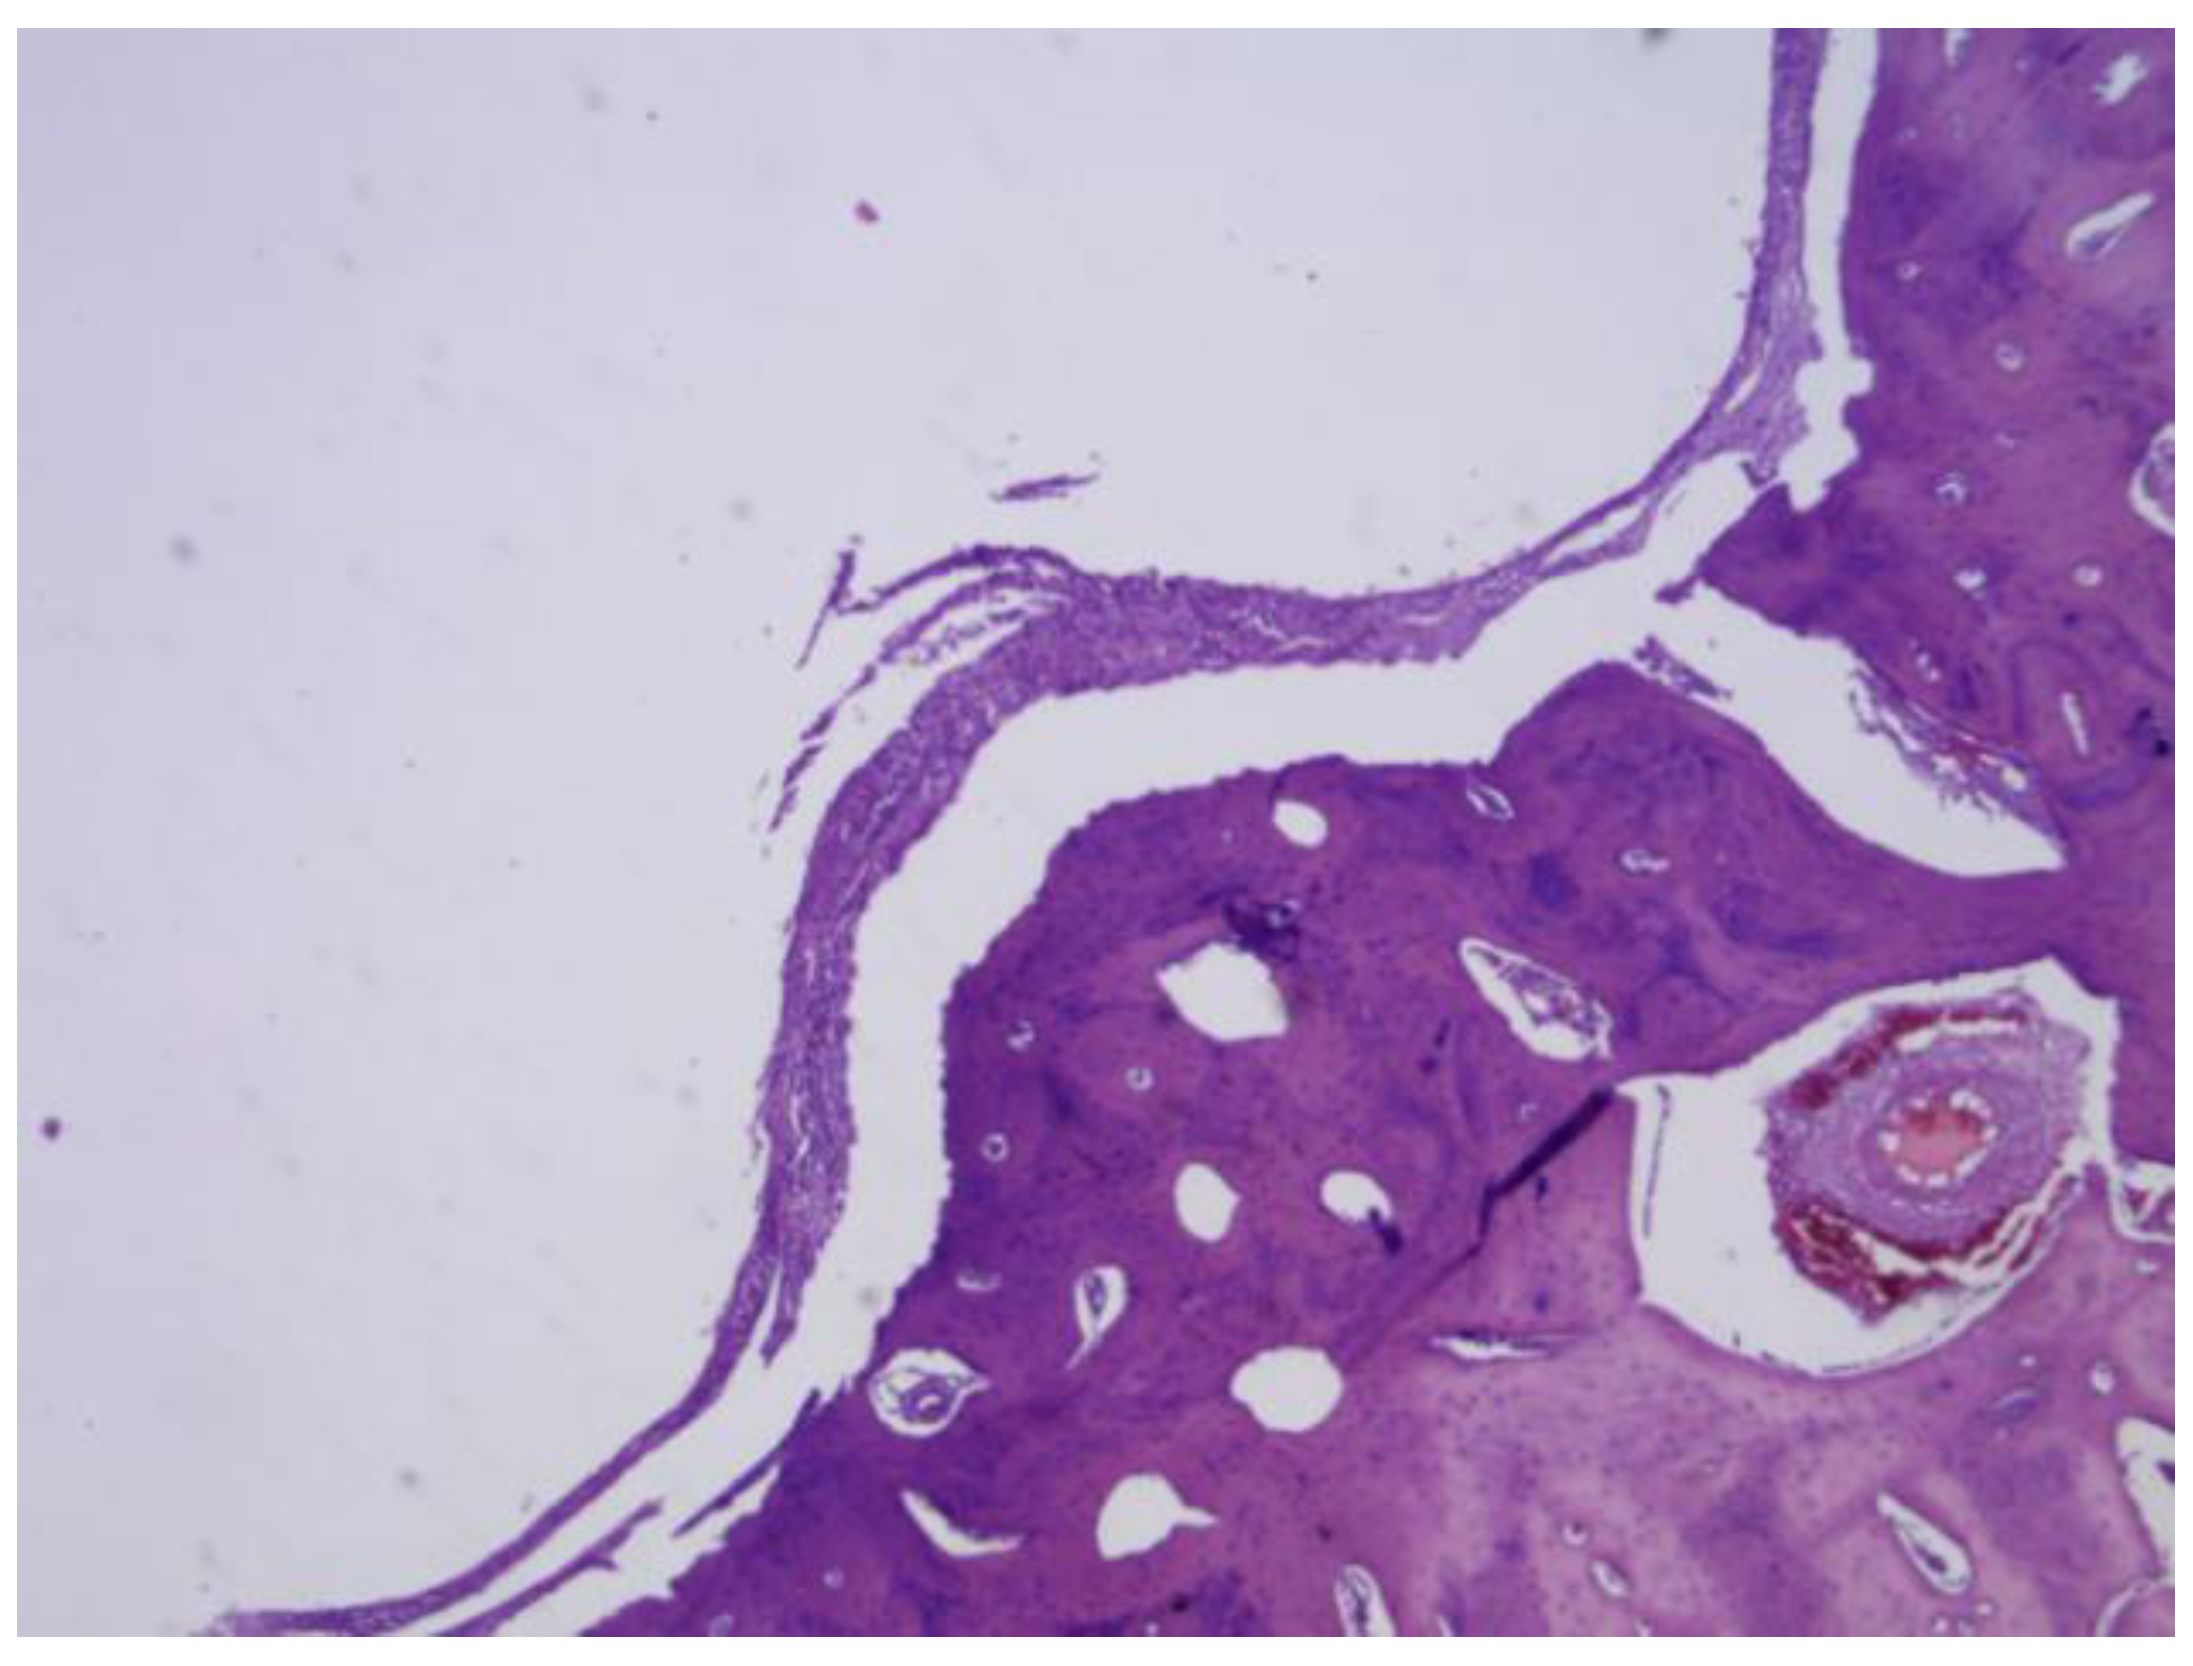

PLDLLA: Histological post-implantation analysis at both the third and fourth months revealed cortical bone in close apposition to the prosthesis, accompanied by mature periprosthetic fibrosis. Effective osteointegration was evident, indicating that the material achieved direct bone contact without the interposition of fibrous tissue a key indicator of stable mechanical and biological integration. The periprosthetic fibrosis and inflammatory response were both mild, with minimal cellular infiltration, reflecting excellent biocompatibility. Scattered neovascularisation was present, supporting ongoing tissue remodelling. Importantly, there were no signs of synovial metaplasia or osteoid formation, further confirming the absence of pathological tissue reactions. Overall, these findings support a stable and successful osseous integration of the PLDLLA implant. (Figure 33)

Figure 33. PLDLLA histological analysis shows cortical bone in close apposition to the prosthesis, accompanied by mature periprosthetic fibrosis.